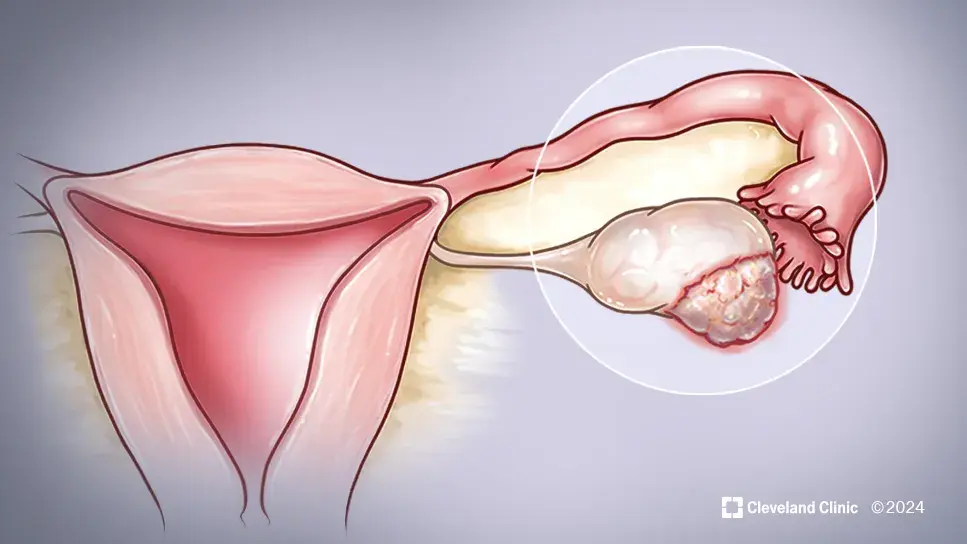

Συμπτώματα καρκίνου των ωοθηκών

Η έγκαιρη διάγνωση είναι καθοριστική για την επιτυχή θεραπεία. Ο καρκίνος των ωοθηκών ιδιαίτερα συχνά διαγιγνώσκεται αργά λόγω ασαφών συμπτωμάτων, γι’ αυτό είναι σημαντική η γνώση του προσωπικού και οικογενειακού κινδύνου σας.